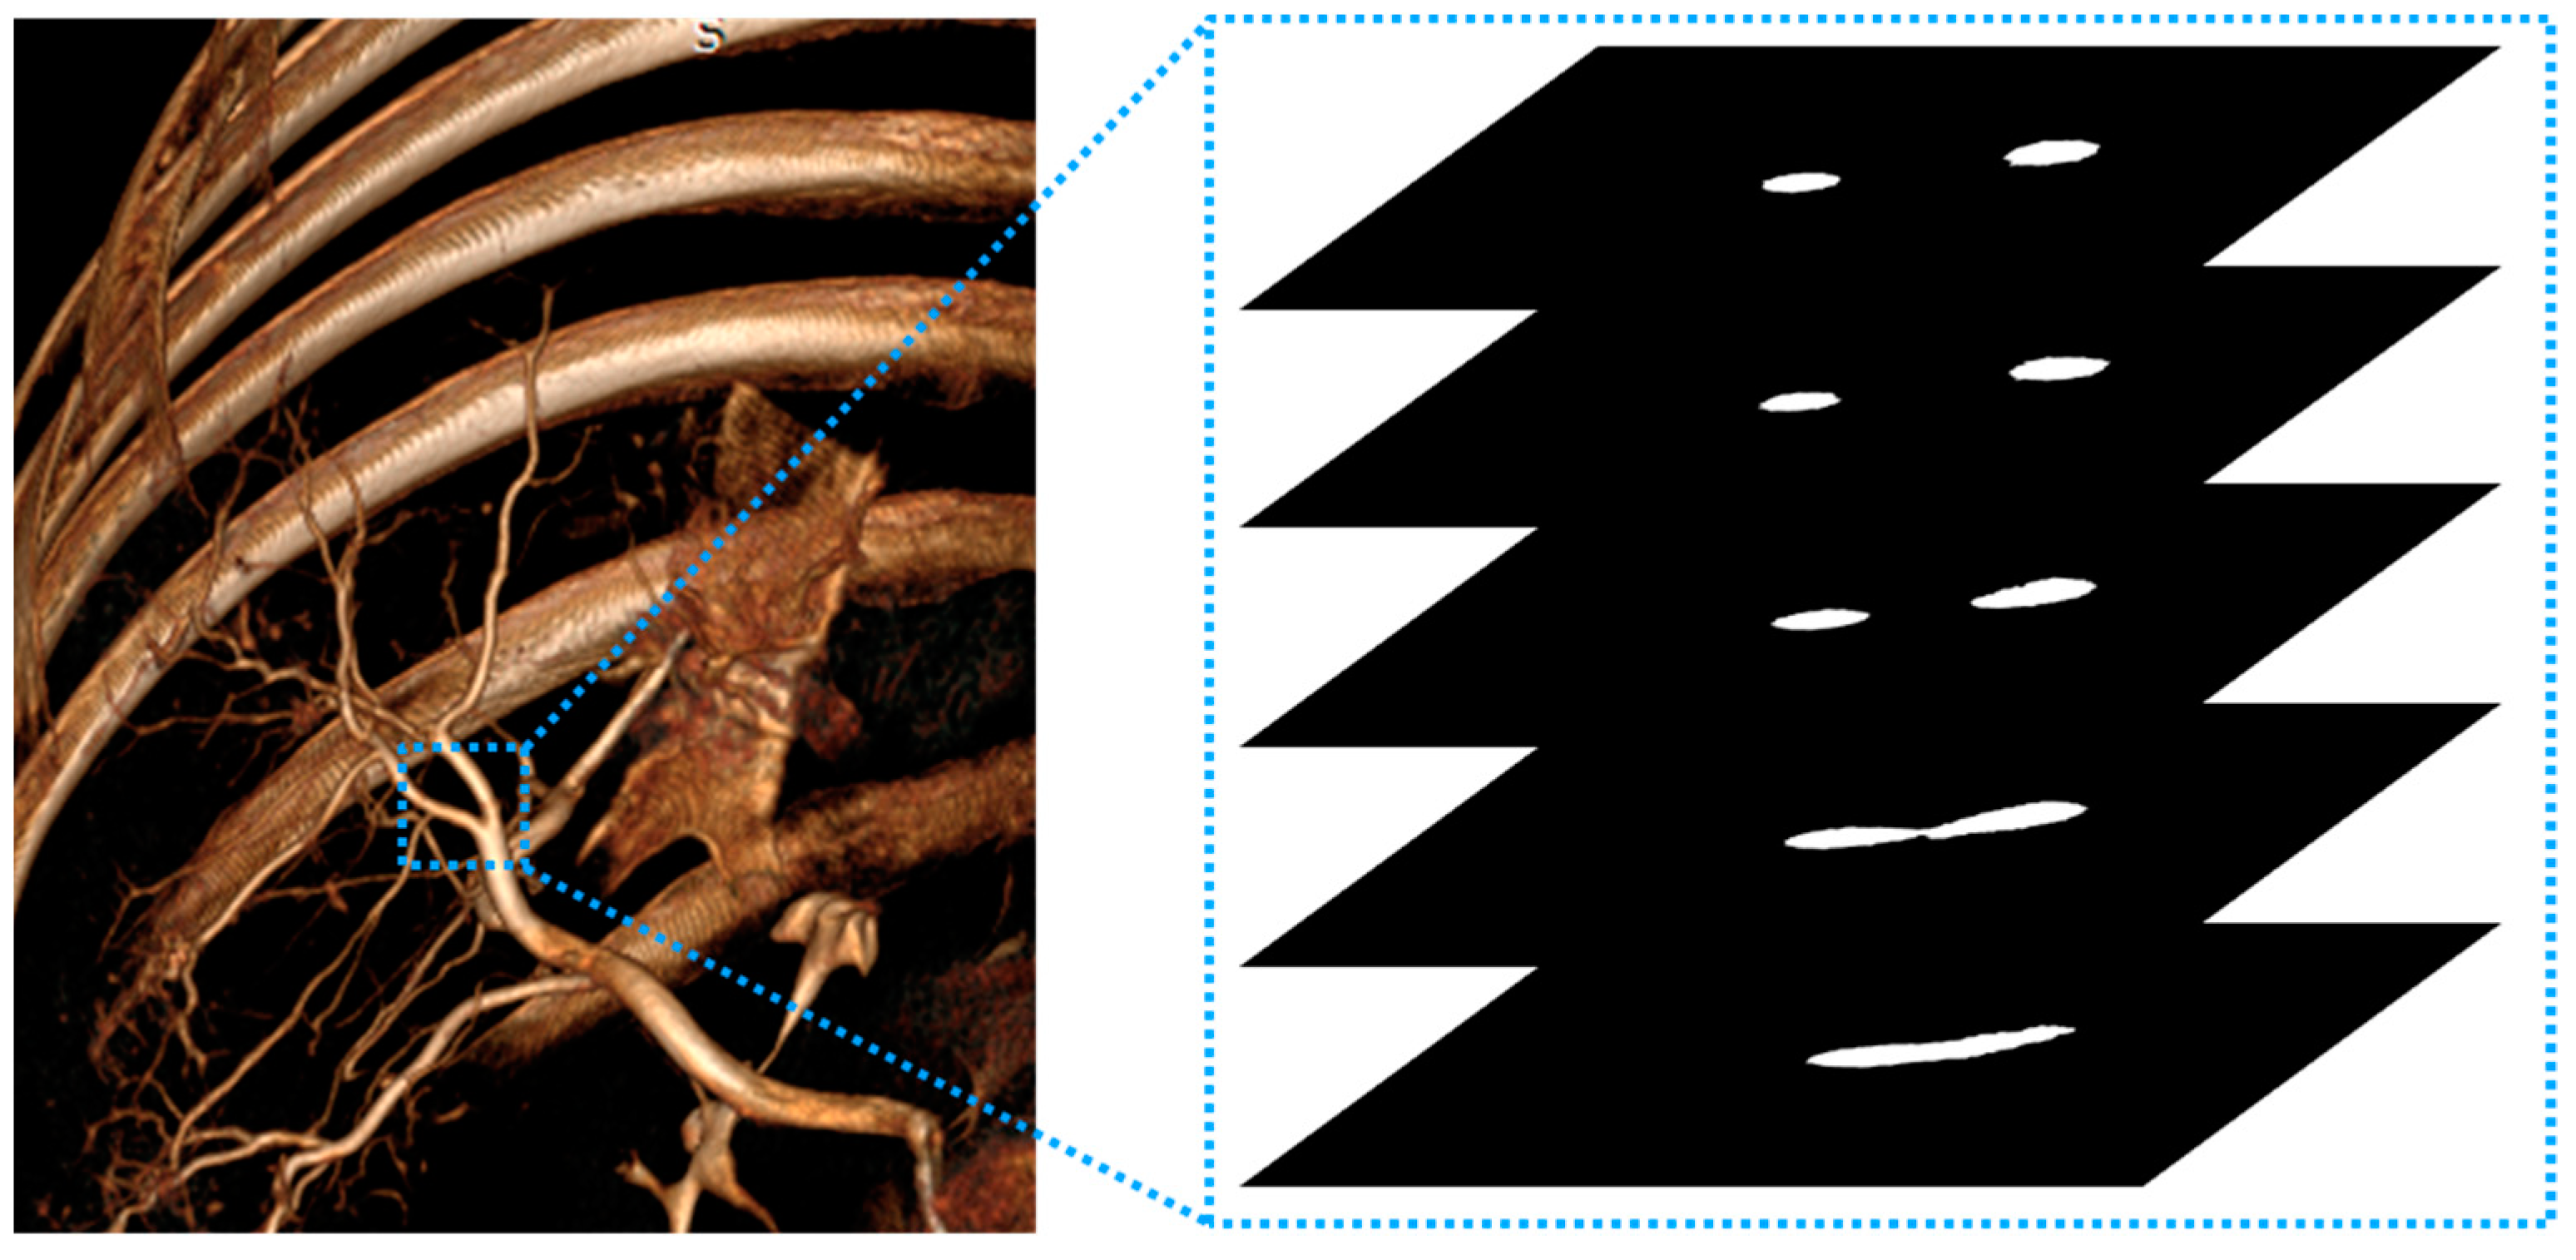

2.2. Motion-Corrected Index

2.3. Experiment 1